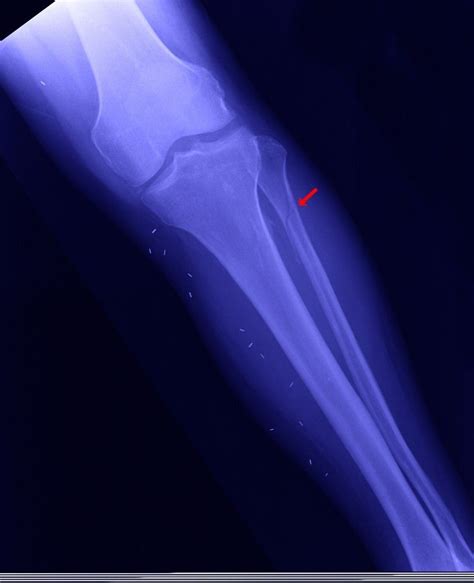

Diagnosis of Proximal Fibula Fracture

Diagnosing a Proximal Fibula Fracture involves a combination of physical examination and imaging tests. The diagnostic process typically includes:

• Physical examination: A healthcare provider will assess the injured area for pain, swelling, and deformity.

• X-rays: Imaging tests to visualize the bone and determine the location and severity of the fracture.

• CT scans or MRI: In some cases, more detailed imaging may be required to assess the extent of the injury and plan treatment.